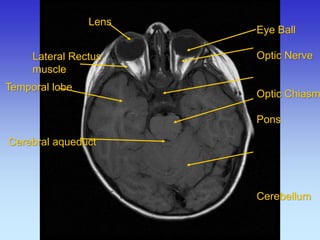

Lens

Cerebral aqueduct

Eye Ball

Optic Nerve

Optic Chiasm

Pons

Cerebellum

Temporal lobe

Lateral Rectus

muscle